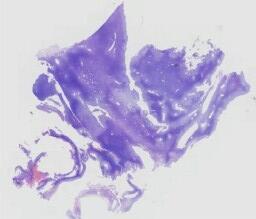

临床资料: 患者,女性,59岁,部位:左侧臀部浅表肿物。临床:左侧臀部结节半年,伴轻度压痛;术中见:左侧臀部褐色结节,边界清楚,质韧。既往史:宫颈恶性肿瘤,具体不详。

大体所见: 带梭形皮瓣的组织一块,大小1.4cm×0.7cm×0.6cm。切面灰白、实性、质中。